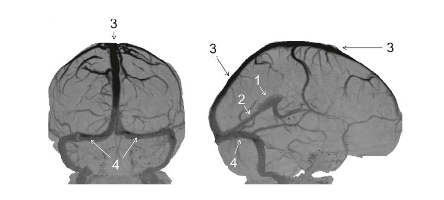

Coupe ?

Légende ?

Coupe ? Légende ?